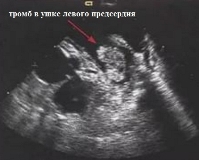

При мерцательной аритмии тромбы обычно локализуются в ушках левых предсердий. Ушко представляет собой выпячивание предсердия (оно похоже на мешочек). Тромбы ушка левого предсердия можно выявить чаще всего только при чреспищеводной Эхо-КГ. С помощью эхокардиографии их обнаружить очень трудно.

Эхокардиографическое (ЭхоКГ) выявление тромбов ЛП затруднено. Существенная часть тромбов формируется в ушке предсердия, которое сложно для визуализации при трансторакальном доступе, особенно у детей. Более того, при трансторакальном доступе при парастернальном сканировании по длинной оси левого желудочка (ЛЖ) и при апикальном изображении ЛП находится вне центра экрана. У взрослых оно дополнительно прикрыто возрастной эмфиземой легких и жировой клетчаткой грудной стенки. Ушко ЛП можно визуализировать при трансторакальном доступе, сканируя парастернально по короткой оси на уровне клапана аорты и направляя датчик чуть вверх и латерально. В этом случае ниже легочной артерии можно увидеть треугольное образование. При апикальном двухкамерном изображении ушко предсердия выводится на экран при легком наклоне датчика вверх [3, 4].

Если при трансторакальном доступе эхогенные массы в ЛП выявляются у пациента с фибрилляцией или стенозом левого атриовентрикулярного отверстия, можно с очень высокой степенью достоверности давать заключение о тромбе. Во всех остальных случаях чувствительность и специфичность трансторакальной ЭхоКГ невысоки. Если у пациента с клинически вероятным тромбом (фибрилляция, расширение предсердия, стеноз атриовентрикулярного отверстия) последнего не выявлено, это не значит, что его нет. Объемное образование ЛП может быть при иных состояниях, а вероятность обнаружения тромба в ушке предсердия при трансторакальном сканирования невысока.

При использовании высокочувствительной трансэзофагеальной ЭхоКГ ЛП практически вплотную прилежит к датчику, возможно использование высокой частоты (7,5 МГц) и, соответственно, разрешения, что позволяет визуализировать мелкие тромбы. Но методика используется в специализированных клиниках, применять ее имеет смысл только в тех случаях, когда результаты будут определять лечение. Важность заключения о наличии тромба ЛП зависит от клинических условий. Например, у пациента с новой фибрилляцией предсердий и эмболическим инсультом наиболее вероятной причиной инсульта является тромб в ЛП независимо от того, визуализируется он или нет. Демонстрация тромба ЛП план лечения инсульта не изменит. Напротив, у пациента с ревматическим митральным стенозом наличие тромба ЛП является противопоказанием к митральной баллонной вальвотомии. Поиск тромба ЛП с помощью трансэзофагеальной ЭхоКГ полностью оправдан перед плановой кардиоверсией, интервенционными и электрофизиологическими процедурами, при которых катетеры или устройства вводят в ЛП (митральная вальвулопластика, абляция фибрилляции предсердий). Поступление крови в ЛП и ее смешивание с фактически стоящим озерком крови в самом предсердии создает эффект спонтанного контрастирования в виде светлых полос завихрения. Феномен спонтанного контрастирования зависит от частоты излучения, режима работы аппарата (степень усиления), опыта исследователя. Появление этого феномена является предтечей тромба и эмболий. Более информативна допплерография. В норме скорость кровотока у взрослых на расстоянии 1 см от устья ушка предсердия в систолу выше 0,4 м/с, а вероятность образования тромба резко повышается при показателе ниже 0,4 м/с.

Возможности чреспищеводной эхокардиографии для выявления тромбов в левом предсердии и особенно левого предсердия хорошо документирована. Обычно такие процедуры проводят для исключения тромба в ушке левого предсердия у пациента, который должен был пройти электрическую кардиоверсию из-за фибрилляции предсердий. Также это исследование полезно у пациентов с долгой историей тяжелого митрального стеноза. УЗИ сердца регистрирует легочную гипертензию, а верхушечная четырехкамерная проекция демонстрирует не только увеличение правого и левого предсердий, но присутствие тромба в левом предсердии. Левые отделы сердца, конечно, не единственное место, где могут возникать тромбы.